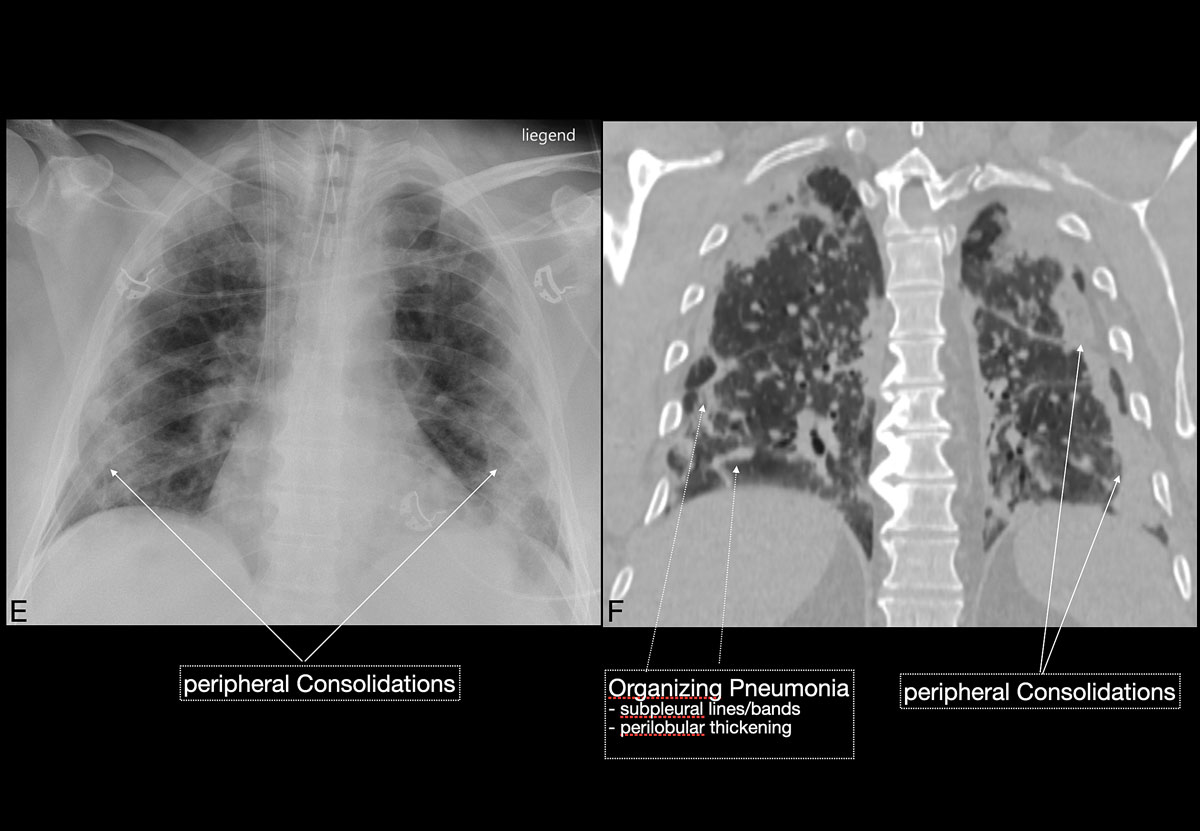

Figure 3 EF Over time the clinical condition worsened, chest x-ray (E) demonstrated persisting, but mildly improving peripheral consolidations, and chest CT (F) demonstrated features of reparative organising pneumonia. The patient’s condition deteriorated and he died from septic and cardiogenic shock 12 days after intubation.

Imaging features in our patient cohort are summarised in table 2 and compared with manifestations observed on CT in Chinese patients [20]. Classic imaging findings are bilateral ground glass opacities with or without areas of consolidation, predominantly with a peripheral or basal lower lobe distribution (figs 3 and 5 ). Unilateral or bilateral ground glass opacities – the hallmark of an early infection (0–4 days) – were observed in almost all COVID-19 patients on chest CT examinations (97% positivity). Given the very subtle appearance of ground glass opacities, their detection on chest x-ray is difficult and often not made prospectively. The second most apparent imaging patterns are consolidations, which are typically multifocal, subpleural/peripheral, or in a peribronchovascular distribution (figs 3 and 5 ). As the disease progresses (5–8 days), the extent of ground glass opacities increases and the amount of consolidation rises (fig. 6). The ground glass opacities progressively transform into consolidative opacities featuring patterns of organising pneumonia of varying extents in the peak stage (10–13 days), before gradually resolving with the patient’s recovery. Typical patterns of organising pneumonia include subpleural lines/bands, perilobular thickening, arcade and atoll signs. Generally, the development of consolidations is a sign of disease progression and is more common in patients above 50 years old and those who have experienced a longer duration of symptoms.